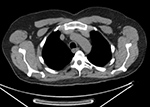

Thyroid imaging with pinhole collimator after the injection of free Tc-99m pertechnetate shows a rounded focal photopenic defect in the region of the left lower thyroid lobe caused by a nonfunctional photomultiplier tube. Focal intense activity seen in the right antecubital region and along the right lateral abdominal wall on Tc-99m MDP scan is related to extravasation of radiopharmaceutical at the injection site with scatter of photons from the forearm to the abdominal wall (narrow angle scatter). Fused axial FDG PET-CT (B), PET axial (C), CT axial (D) and MIP PET (E) images demonstrate intensely FDG avid lymph node in the right axilla. Infiltration of FDG at the injection site in right antecubital fossa results in lymphoscintigraphy with FDG migrating to the regional nodal basin via the lymphatic ducts.

Fused axial FDG PET-CT (B), PET axial (C), CT axial (D) and MIP PET (E) images, demonstrate intensely FDG avid lymph node in the right axilla. Infiltration of FDG at the injection site in right antecubital fossa results in lymphoscintigraphy with FDG migrating to the regional nodal basin via the lymphatic ducts. Technetium 99m MDP whole body bone scan shows photopenic defect on the midline pelvis from the attenuation of a belt buckle.